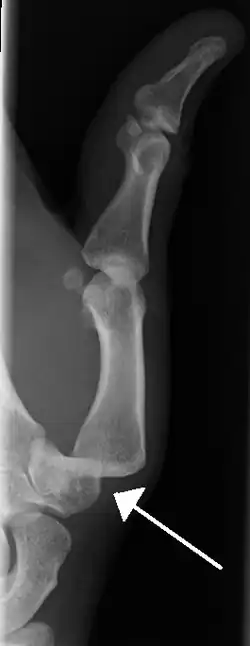

Radiograph of right fifth finger dislocation

• Finger

• Interphalangeal (IP) or metacarpophalangeal (MCP) joint dislocations[41]

• In the United States, men are most likely to sustain a finger dislocation with an incidence rate of 17.8 per 100,000 person-years.[42] Women have an incidence rate of 4.65 per 100,000 person-years.[42] The average age group that sustain a finger dislocation are between 15 and 19 years old.[42]

• The most common dislocations are in the proximal interphalangeal (PIP) joints.[8]